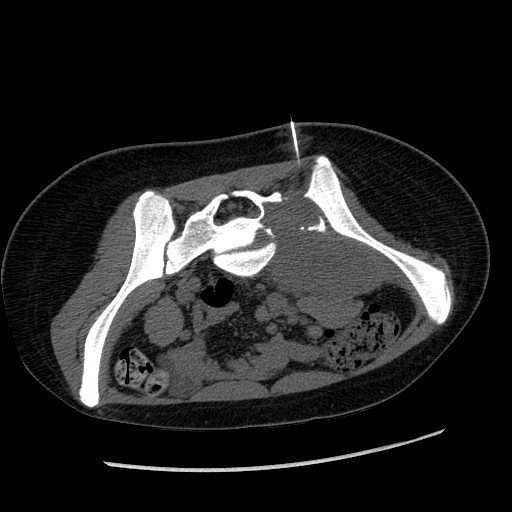

1.    The patient was a 3 year-old girl with the chief complain of left lower extremity that extended to the right side. Imaging demonstrated a large sacral mass that mainly affects her left side. These features are not sufficient for a definitive diagnosis but which of the following be the most likely diagnosis? Answer

CT taken at the time

of the needle biopsy

(needle is shown here)

MRI FNA

Diff Quick Stain

Permanent section

Hematoxylin & Eosin Stain